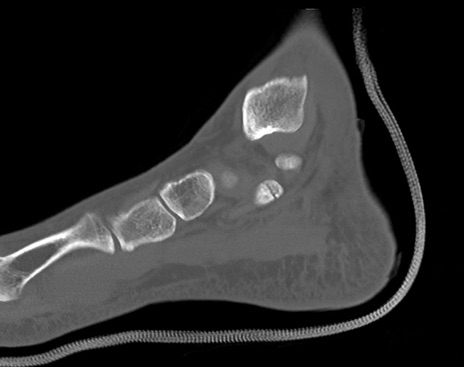

症例37 左足関節CT(矢状断像)

【症例】50歳代男性

【主訴】左踵部の痛み、腫脹

【現病歴】4日前に1.5m程度の高さのトラックの荷台から荷物と一緒に転落し、左足部を打撲。近医受診し、当院へ紹介受診となる。

【身体所見】左踵部の腫脹、圧痛あり。

左足関節CT